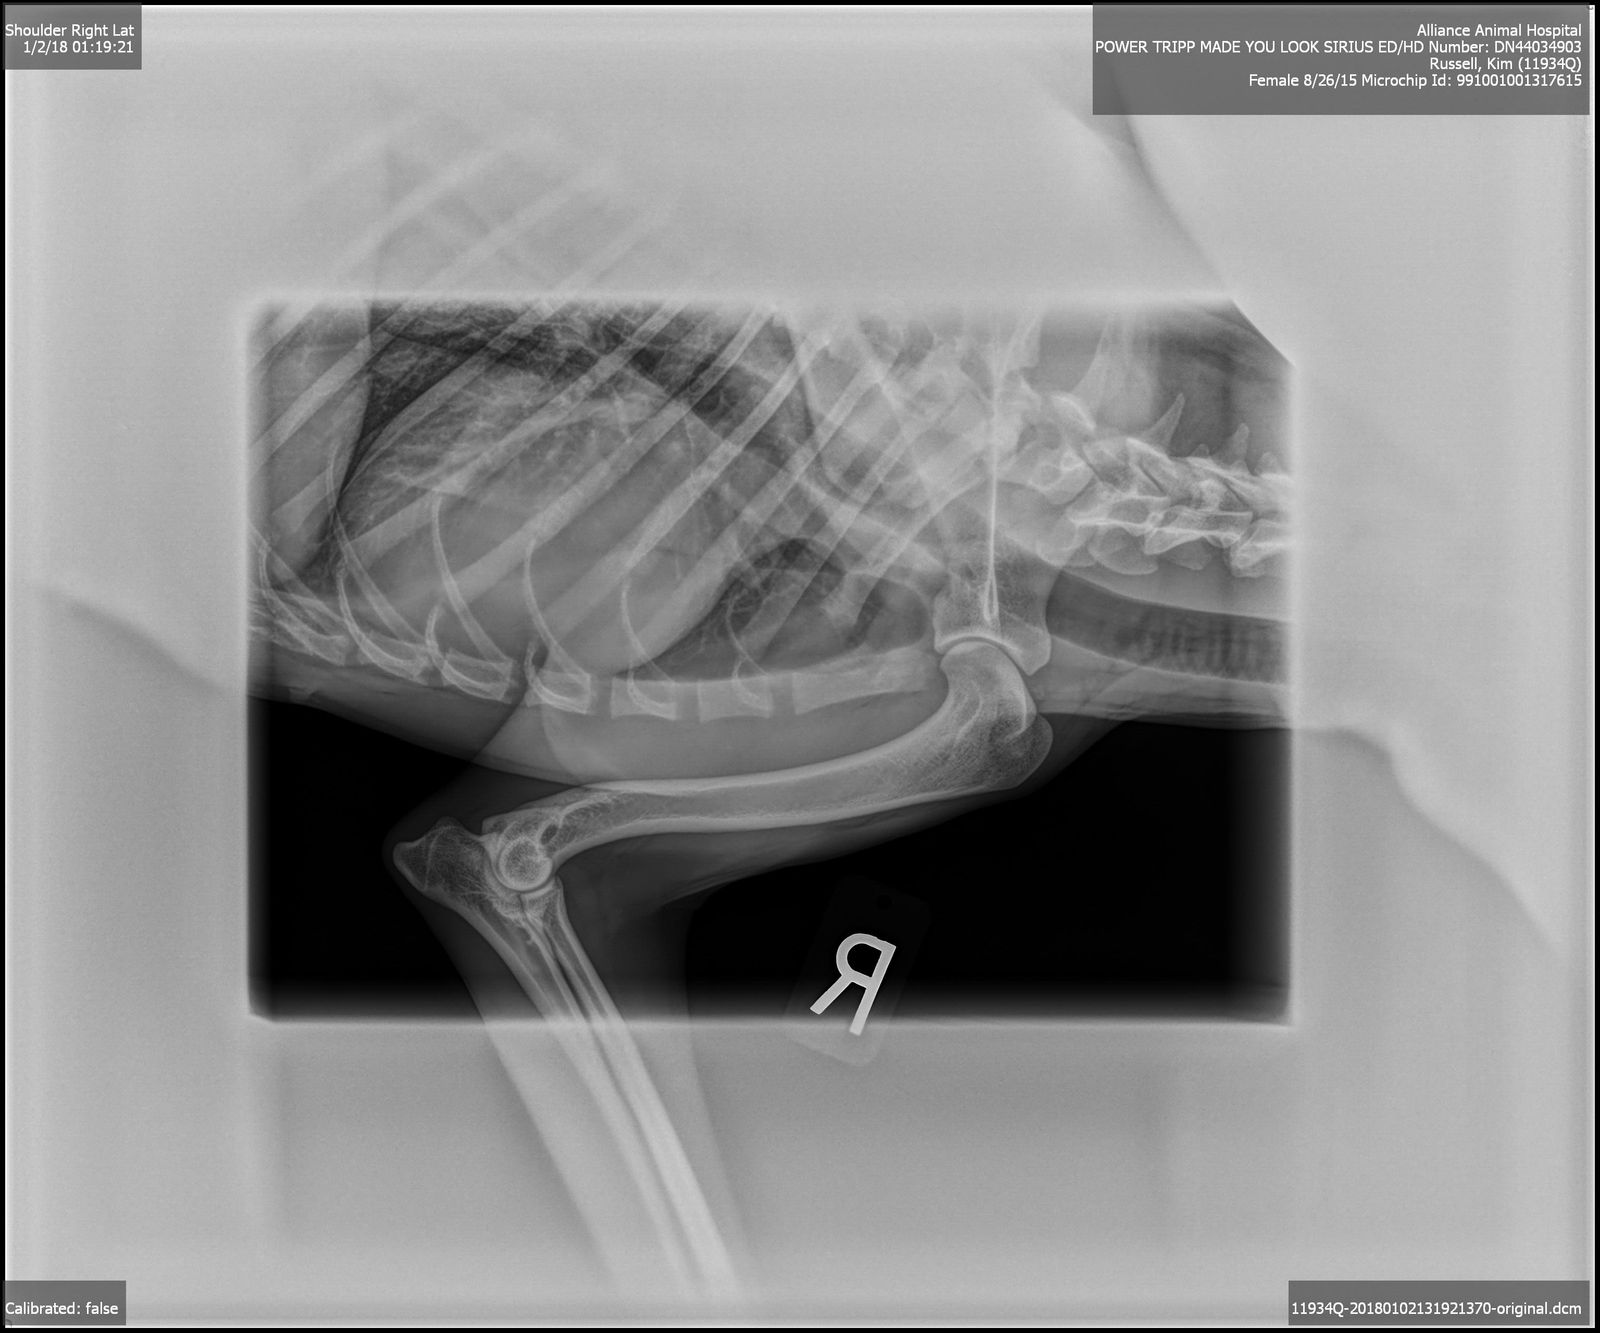

OFA Excellent, Shoulders and Elbows Normal, CEA/EAOD/CM/DM/MDR1/TNS/IGS/SN Normal,

2015/8/25AKC DN44034903 OFA Excellent, Shoulders and Elbows Normal, CEA/CM/DM/MDR1/TNS/IGS/SN Normal, BAER Normal